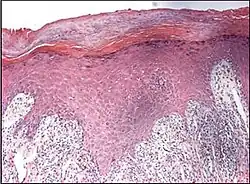

| Lichen planus | Irregular epidermal hyperplasia with a jagged “sawtooth” appearance, compact hyperkeratosis or orthokeratosis, foci of wedge-shaped hypergranulosis, basilar vacuolar degeneration, slight spongiosis in the spinous layer, and squamatization. The dermal papillae between the elongated rete ridges are frequently dome shaped. Necrotic keratinocytes can be observed in the basal layer of the epidermis and at the dermal-epidermal junction. Eosinophilic remnants of anucleate apoptotic basal cells may also be found in the dermis and are referred to as “colloid or civatte bodies”. Whickham striae are usually seen in the areas of hypergranulosis. Vacuolar degeneration at the basal layer may be noted leading to focal subepidermal clefts (Max Joseph spaces). Squamatization occurs as a result of maturation and flattening of cells in the basal layer. It happens in areas of marked hypergranulosis with prominence of the sawtooth pattern of rete ridges. Wedge-shaped hypergranulosis can occur in the eccrine ducts (acrosyringia) or hair follicles (acrotrichia). In the hypertrophic subtype, the associated hyperkeratosis, parakeratosis, hypergranulosis, papillomatosis, acanthosis, and hyperplasia markedly increased with thicker collagen bundles forming in the dermis. Moreover, the rete ridges are more elongated and rounded as opposed to the typical sawtooth pattern. In atrophic LP, loss of the rete ridges and dermal fibrosis is prominent. In vesiculobullous LP, the disease progression is quicker. Hence, some of the distinctive features such as hyperkeratosis, hypergranulosis, or dense lymphocytic dermal-epidermal infiltrate may not be present. LP lesion may resolve with residual hyperpigmentation caused by a persistent increase in the number of melanophages in the papillary dermis.[9] | ![]() |